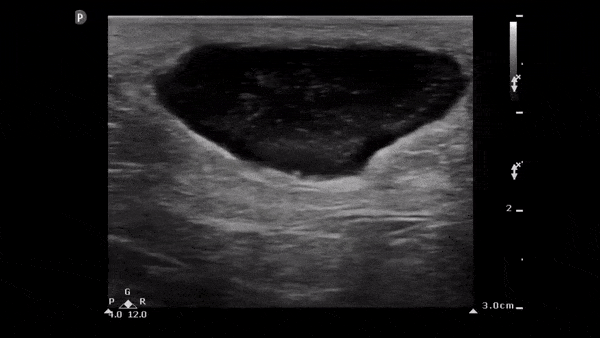

One Minute Image Review

One-Minute Image Review: High yield bite sized learning! Voice annotation of both normal and abnormal point of care ultrasound clips!